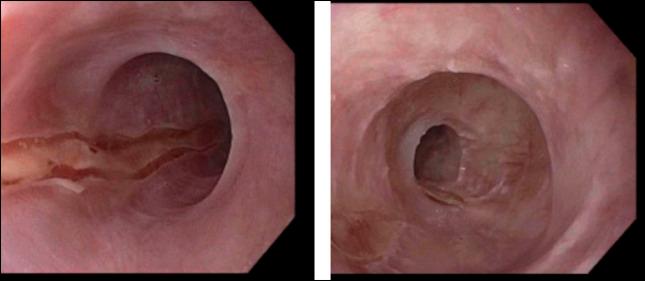

Although rarely reported, esophageal lichen planus is a chronic inflammatory disease that can lead to debilitating symptoms. It is reported to affect adult women in the fourth and fifth decades of life. Treatment ranges from medical therapy to endoscopic dilation. Owing to underdiagnoses and limited data on therapies, little guidance is provided in the literature regarding treatment of refractory cases. We report a case of a 68-year-old woman with esophageal lichen planus who had symptoms and lack of histological improvement despite being on budesonide and mycophenolate. She was then transitioned to upadacitinib 30 mg daily and had significant symptomatic and endoscopic improvement.

尽管食管扁平苔藓鲜有报道,但它是一种可导致使人衰弱症状的慢性炎症性疾病。据报道,该病会影响处于四五十岁年龄段的成年女性。治疗方法从药物治疗到内镜扩张不等。由于诊断不足以及关于治疗的数据有限,文献中对于难治性病例的治疗几乎没有提供指导。我们报告一例68岁患有食管扁平苔藓的女性病例,尽管使用了布地奈德和霉酚酸酯,但她仍有症状且组织学上没有改善。随后她改用乌帕替尼,每日30毫克,症状和内镜检查结果都有显著改善。